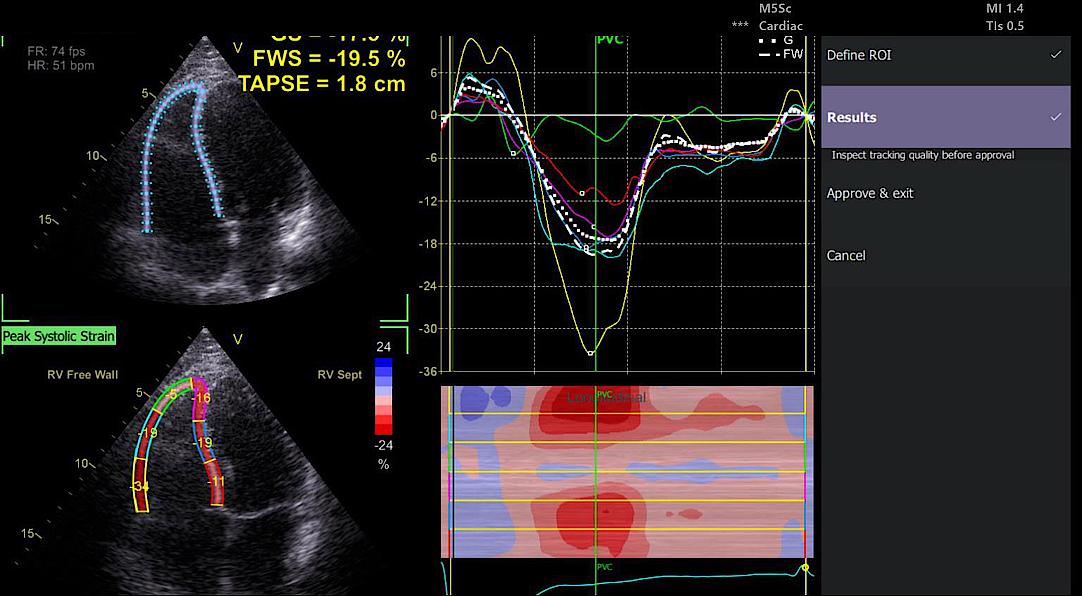

Analyse hémodynamique avancée avec Vivid™

La plateforme Vivid™ combine une imagerie cardiaque de haute précision avec des outils d’analyse hémodynamique avancés, essentiels pour les réanimateurs. Vivid aide à évaluer la fonction cardiaque en temps réel, soutenant ainsi les décisions critiques.